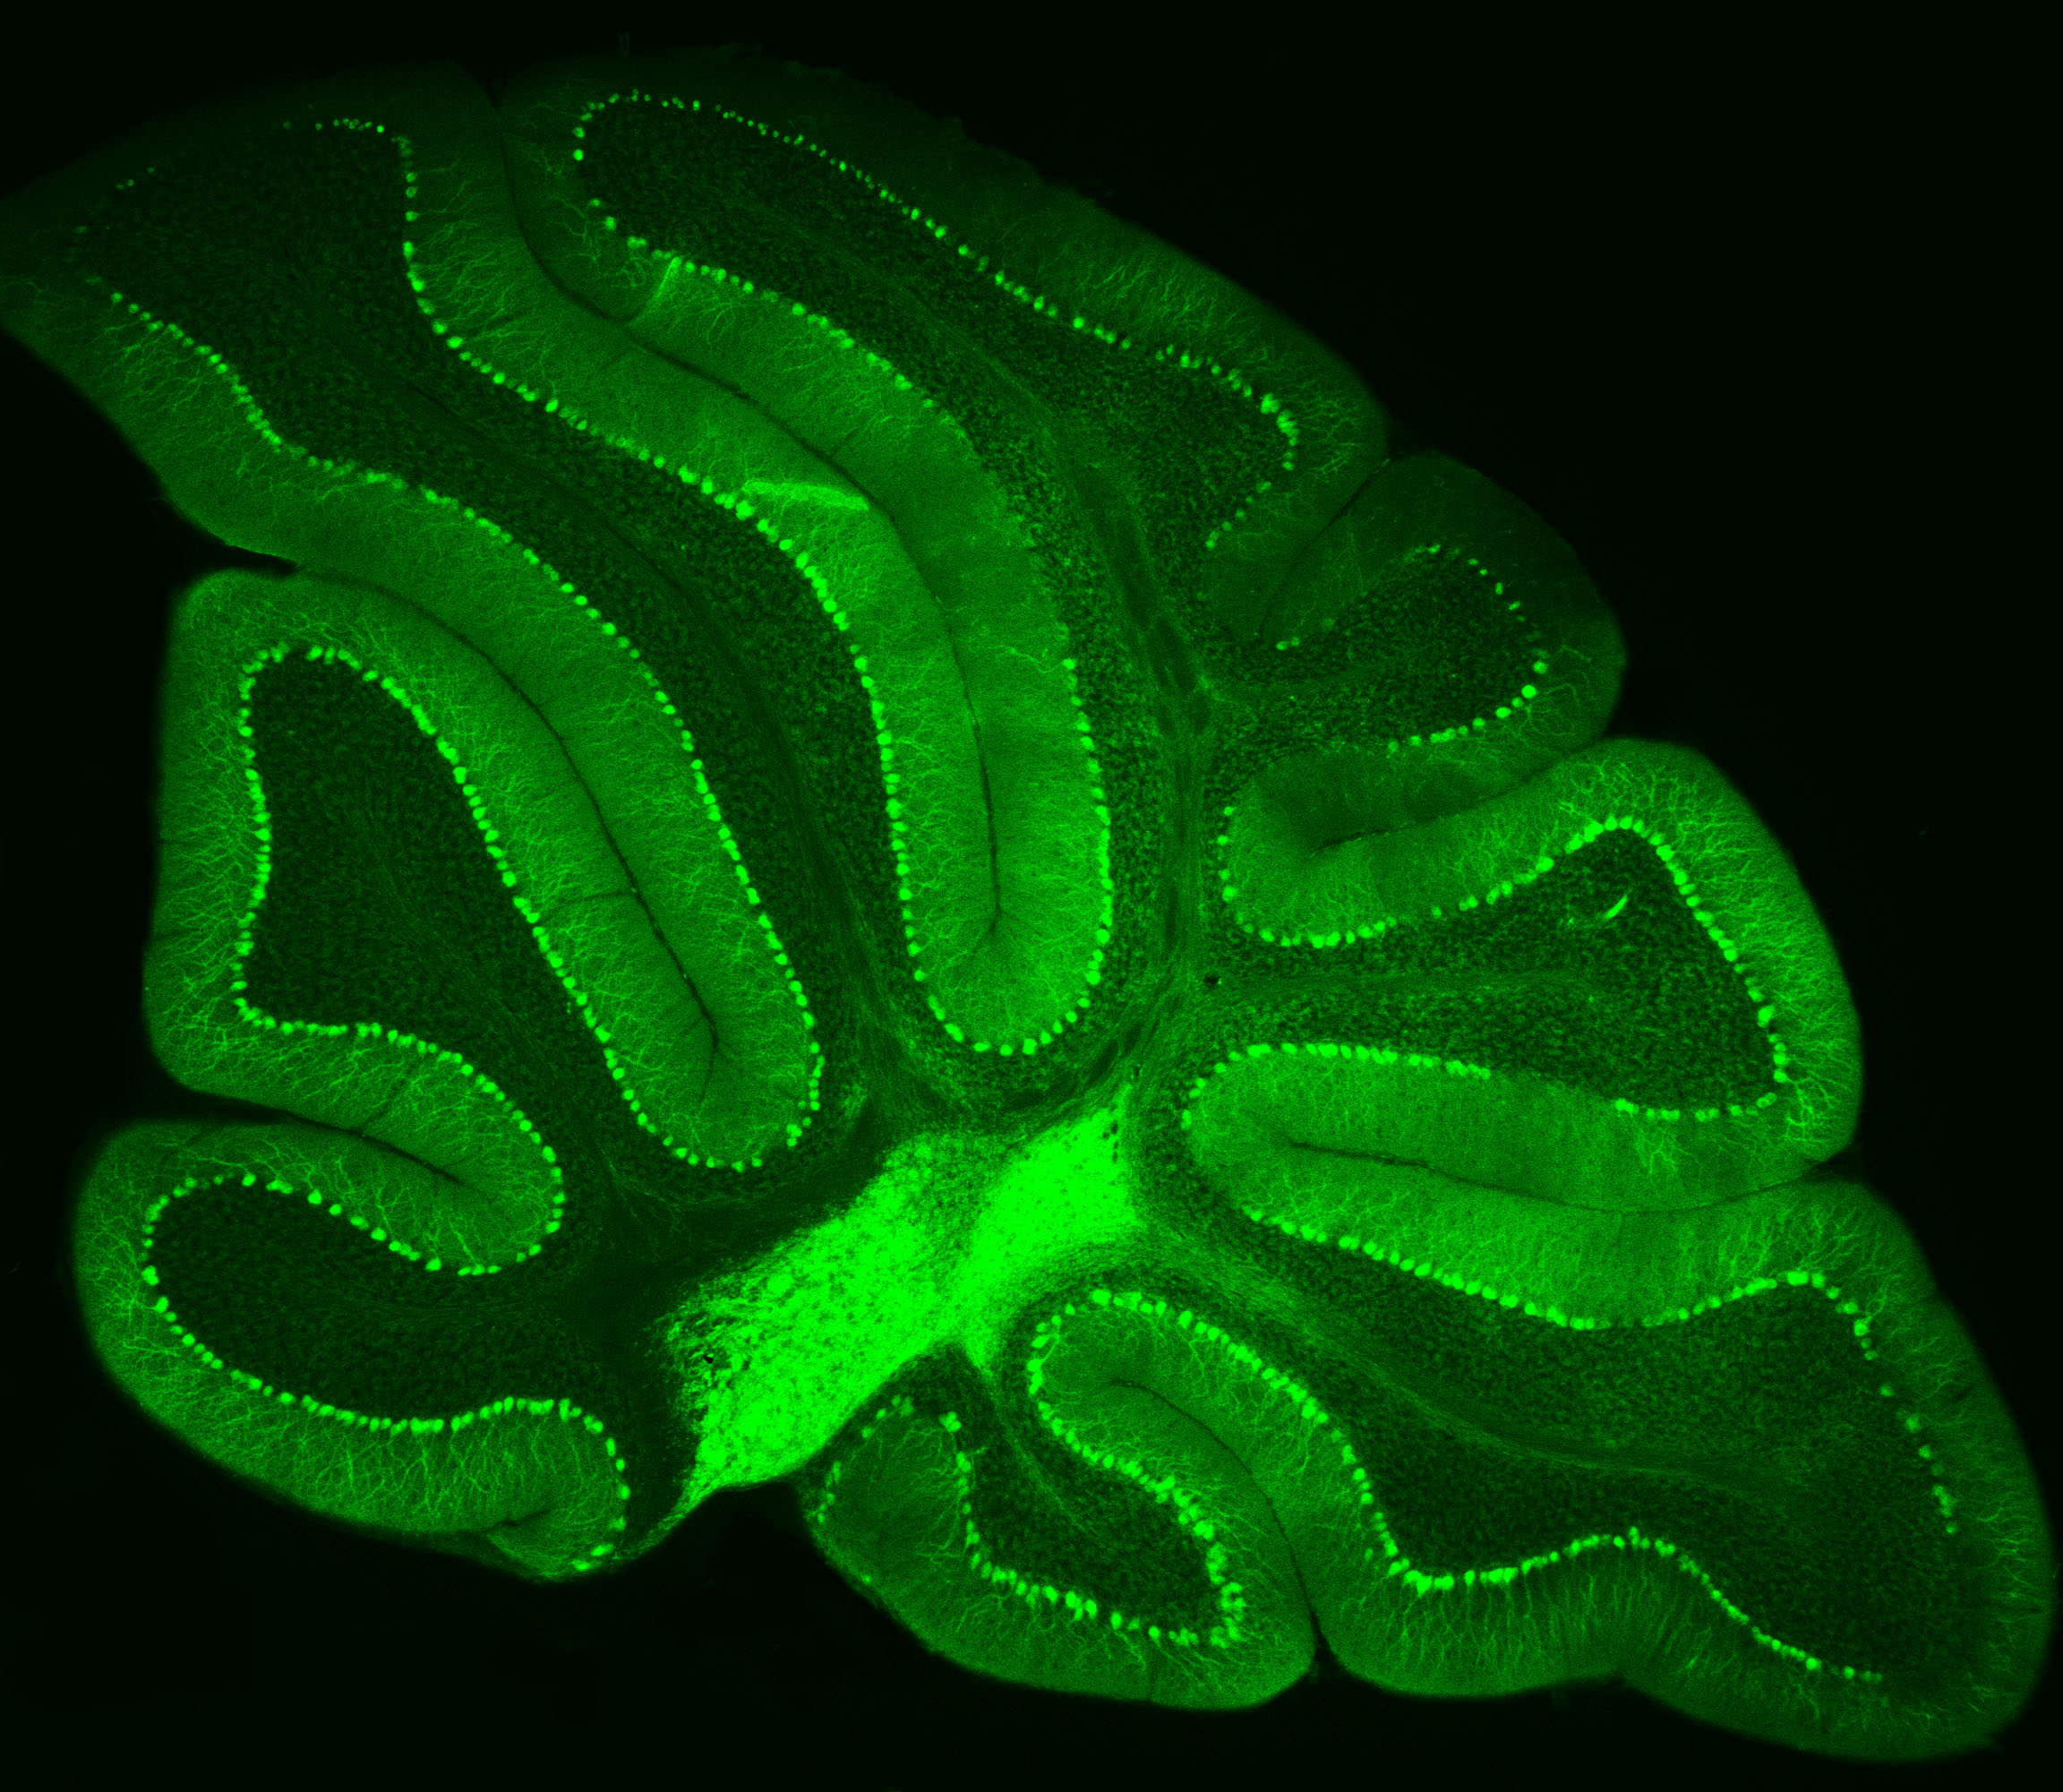

Purkinje neurons from an animal model are labeled with green fluorescent protein (GFP), which causes them to glow bright green. Credit: Pennington Biomedical

At Pennington Biomedical Research Center, scientists often study the brain by highlighting specific cells so they can be seen more clearly under a microscope. This technique was recently used by Dr. Yanlin He, associate professor and director of the Brain Glycemic and Metabolism Control Laboratory, who is examining Purkinje neurons in the cerebellum.

Purkinje neurons are best known for helping control movement and motor learning, but researchers are discovering they may have other important roles in the body as well, such as controlling energy balance and blood sugar.

By making these neurons glow green, Dr. He and his team can see their complex branching shapes and how they connect within the cerebellum’s neural network.

This technique also allows researchers to perform electrophysiology recordings, which measure the electrical activity of the cells in a laboratory setting. Their work could help scientists better understand how the brain helps regulate metabolism and overall health.